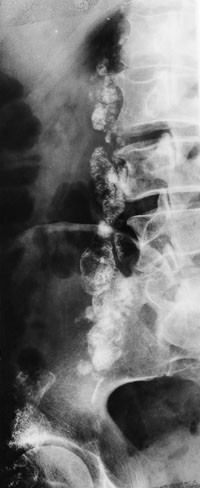

Ved Røntgenavdelingen, Rogaland sjukehus ble det i 1952 utført fistulografi på en pasient med en abscess i venstre lyskeregion. Det fettløselige kontrastmiddel Iodipin (Bayer) ble benyttet. Kontrastmidlet fylte tynne kanaler fra lyskeregionen, og på bilder tatt noe senere kunne man se akkumulasjon av kontrastmiddel i ovale danninger foran iliosakralleddet. Bruun og Engeset antok at de fremstilte strukturer var lymfekar og lymfeknuter. Ettersom det ikke forelå noen metode for undersøkelser av dypereliggende lymfeknuter, besluttet de å forsøke tilsvarende injeksjon hos andre pasienter med forstørrede lyskelymfeknuter. De fant at langsom injeksjon i forstørrede lymfeknuter tillot røntgenologisk fremstilling av både lymfeårer og lymfeknuter i bekkenet og langs lumbalcolumna. I 1956 publiserte de sine resultater fra 11 pasienter i Acta Radiologica. Det fremgår at kontrastmidlet ble deponert i lymfeknutene gjennom lang tid. Dermed kunne lymfeknutenes størrelse og struktur vurderes og responsen på behandling monitoreres på kontrollbilder uten fornyet kontrastinjeksjon. Bruun og Engeset prøvde ut forskjellige typer kontrastmidler uten å finne bedre midler enn det først benyttede, fettløselige Iodipin. For visualisering av lymfeknuter hos pasienter som ikke hadde forstørrede palpable knuter i lysken, foreslo Bruun og Engeset injeksjon i lymfekar på fotryggen med Kinmonths teknikk. Det var nettopp en kombinasjon av de to metoder som gjorde at lymfografiundersøkelsen fikk sitt gjennombrudd på verdensbasis.

Bruun og Engesets bidrag til lymfografimetoden medførte nye muligheter til studium av sykdomsutbredelse, spesielt av primære og sekundære maligne tilstander i lymfeknutene. Metoden tillot også langt bedre monitorering av progrediering eller regresjon i forskjellige faser av behandlingen. I 1960- og 1970-årene var metoden i rutinemessig bruk ved moderne onkologiske sentre verden over. Flere tusen artikler om lymfografi er publisert siden Bruun og Engesets pionerarbeid.